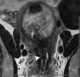

Leiomyoma of cervix

May Cause

Bladder outlet obstruction

Cervical mass